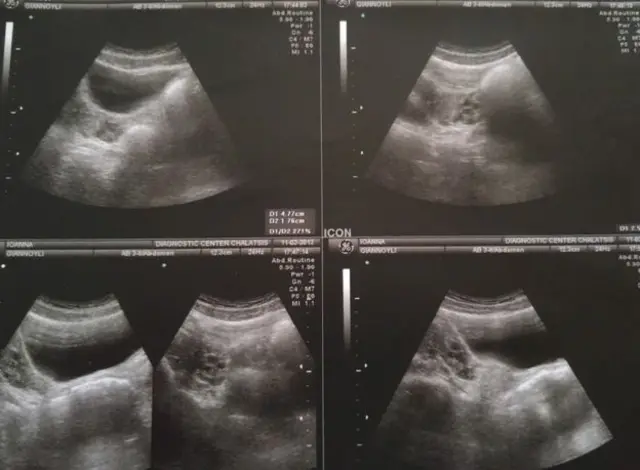

جوآنا جیانولی، ۲۷ ساله، از بدو تولد بدون رحم، گردن رحم و مهبل فوقانی متولد شده است. در این گزارش، او از چالشهایی که این بیماری مادرزاد برای او به وجود آورده میگوید - نقص عضوی که از هر ۵۰۰۰ زن در جهان فقط گریبانگیرِ یک نفر میشود.

برای همین وقتی شانزده ساله شدم، من را به بیمارستانی فرستاد که میتوانستند معاینهام کنند. آنجا بود که تشخیص دادند که مشکل من سندرم روکیتانسکی است و چون بدون مهبل متولد شده بودم، دکترها تصمیم گرفتند یک مهبل جدید برایم بسازند که بتوانم رابطه جنسی داشته باشم.

- بیماریای است مادرزاد در زنان، که به واسطه آن فرد بدون رحم، گردن رحم و مهبل فوقانی متولد میشود و یا این اعضا به صورت ناقص در او شکل میگیرند.